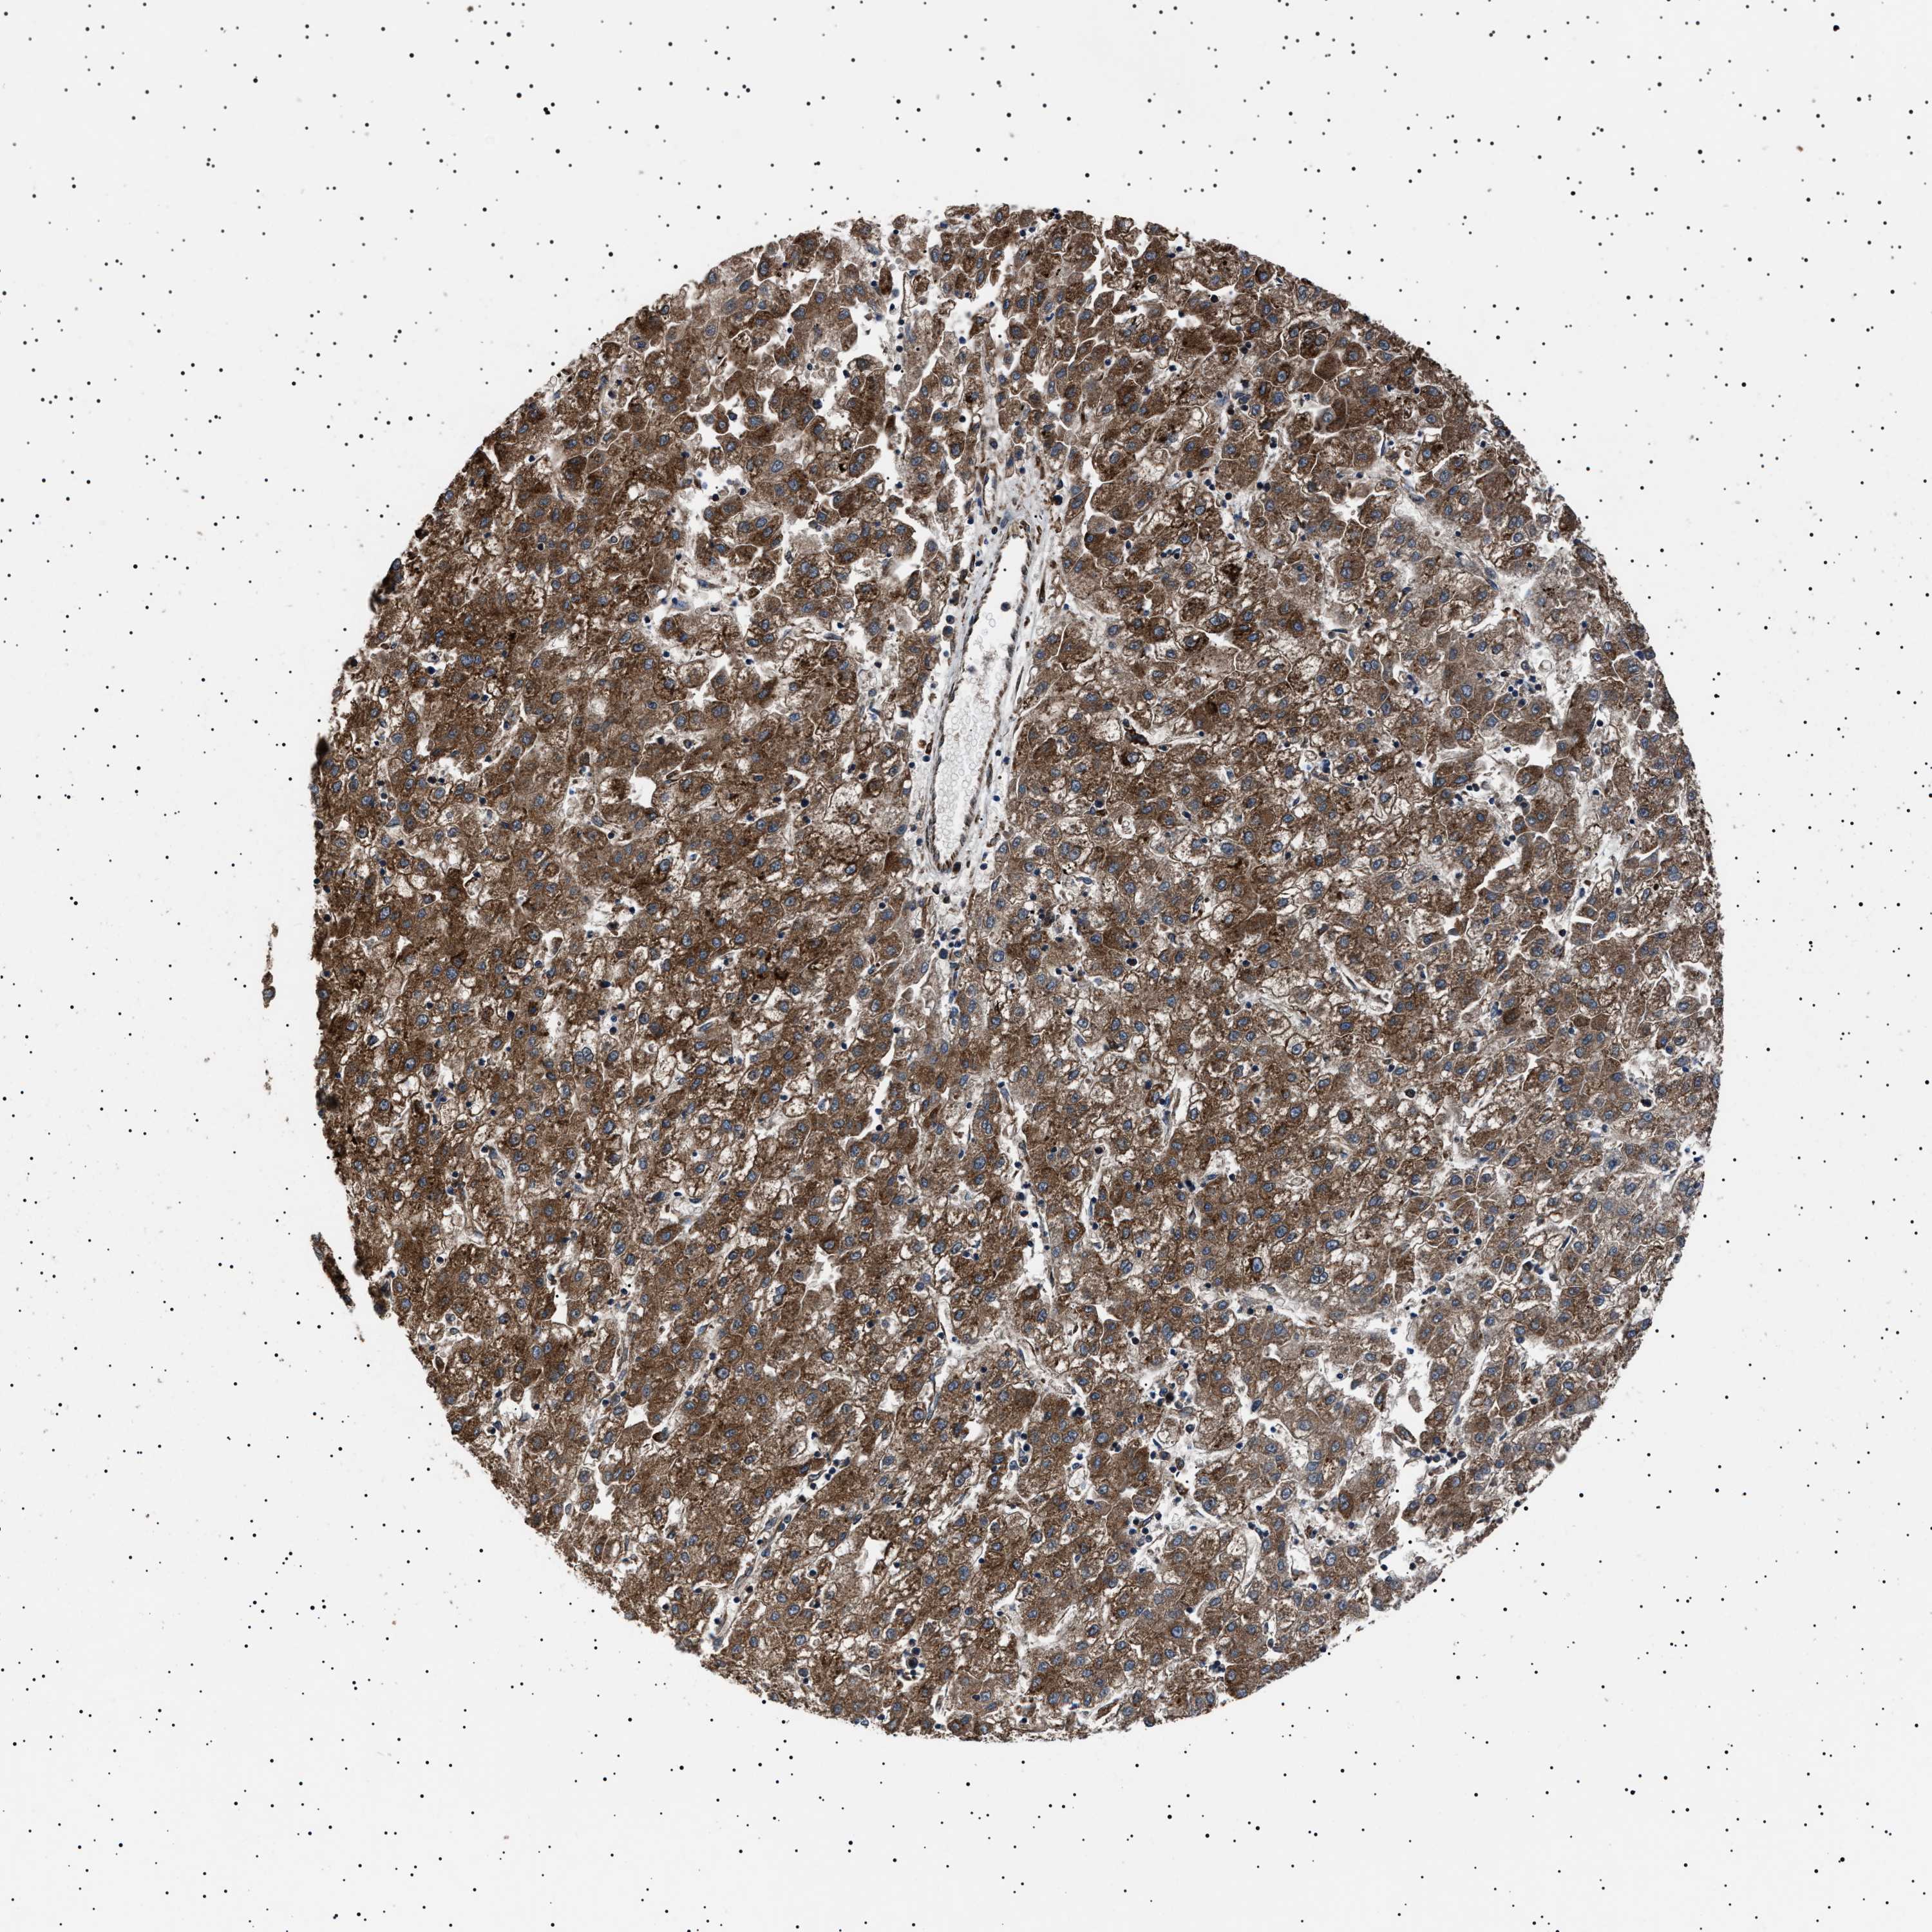

LIVER CANCER - Protein expressioni

A mouse-over function shows sample information and annotation data. Click on an image to view it in a full screen mode. Samples can be filtered based on level of antibody staining by selecting one or several of the following categories: high, medium, low and not detected. The assay and annotation is described here.

Note that samples used for immunohistochemistry by the Human Protein Atlas do not correspond to samples in the TCGA dataset.

Antibody stainingi

Antibody staining in the annotated cell types in the current human tissue is reported as not detected, low, medium, or high, based on conventional immunohistochemistry profiling in selected tissues. This score is based on the combination of the staining intensity and fraction of stained cells.

Each image is clickable and will lead to virtual microscopy that enables deeper exploration of all samples and also displays staining intensity scores, fraction scores and subcellular localization as well as patient and tissue information for each sample.

Antibody HPA001915

Antibody HPA021542

Staining

High

Medium

Low

Not detected

Intensity

Strong

Moderate

Weak

Negative

Quantity

>75%

75%-25%

<25%

None

Location

Nuclear

Cytoplasmic/membranous

Cytoplasmic/membranous,nuclear

Cholangiocarcinoma

Carcinoma, Hepatocellular, NOS